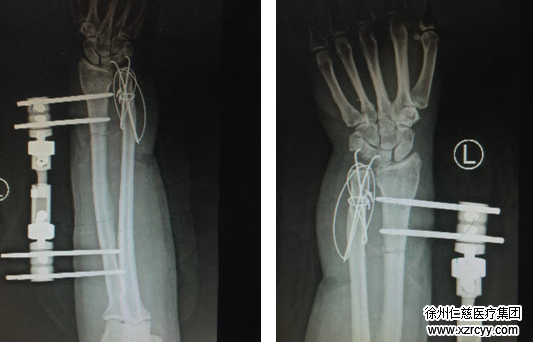

“患者来到我们医院后,生命体征不稳定,左前臂接近毁损状,基本上被判了‘死刑’。但看着患者家人不愿放弃的眼神,我们医护人员的意志也更加坚定了,保肢,无论如何都要保肢!”唐洪伟医生说,患者肢体污染非常严重,伤口贯通,肌肉毁损,伤口内有大量辣椒粉末等残留。术中给予反复冲洗,清创,血管移植,将血管、神经、肌肉、肌腱进行修复,并用外固定支架固定住粉碎性骨折的桡骨,用克氏针和钢丝将骨折的尺骨进行内固定,手术一切顺利。目前患者的再植肢体已经成活,正处于康复阶段。